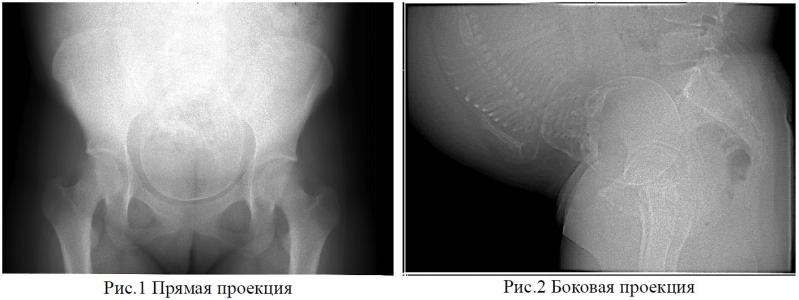

Цифровая рентгенопельвиометрия в акушерской практике

На выставке Здравоохранение 2009 в павильоне №1 на стенде 1С23 разработчики аппарата для цифровой рентгенопельвиметрии внутренних размеров малого таза ознакомят с методикой обследования. Аппарат рекомендован для проведения рентгенопельвиметрии (письмо МЗ РФ от 26.11.2002 №2510/11869-02-32) в перинатальных медицинских центрах.